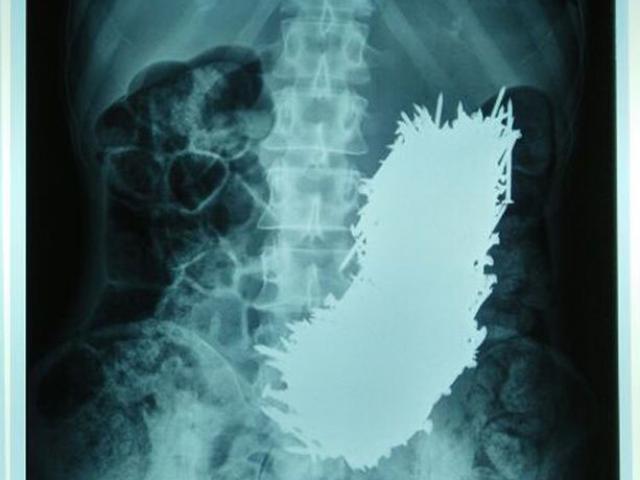

Sau khi các bác sĩ kiểm tra đã phát hiện ra có rất nhiều con bạch thuộc kích thước cực nhỏ bám thành từng chùm dính chặt trong khoang miệng người phụ nữ này. Bác sĩ đã phải cố gắng gỡ bỏ những “hung thủ tí hon” này khỏi khu vực nướu, lưỡi và má của “nạn nhân”.

Báo cáo của bệnh viện ghi lại cho thấy, người phụ nữ này thay vì nuốt chửng đã nhai con bạch tuộc sống khi ăn. Điều này khiến cơ quan sinh sản của con bạch tuộc bị vỡ ra và có cơ hội thụ tinh ngay trong khoang miệng.

“Có những vi khuẩn rất nhỏ màu trắng bị mắc kẹt trong màng nhầy của lưỡi, má và nướu của bệnh nhân đã được loại bỏ hoàn toàn. Sau khi được lấy ra ngoài, các chuyên gia xác định được đây chính là tinh trùng của bạch tuộc”.